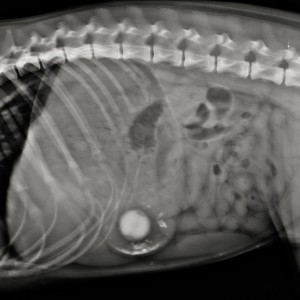

The objective of this multicentre, retrospective, observational study was to describe clinical examination and thoracic CT (TCT) findings in cats after trauma, and to identify physical examination...